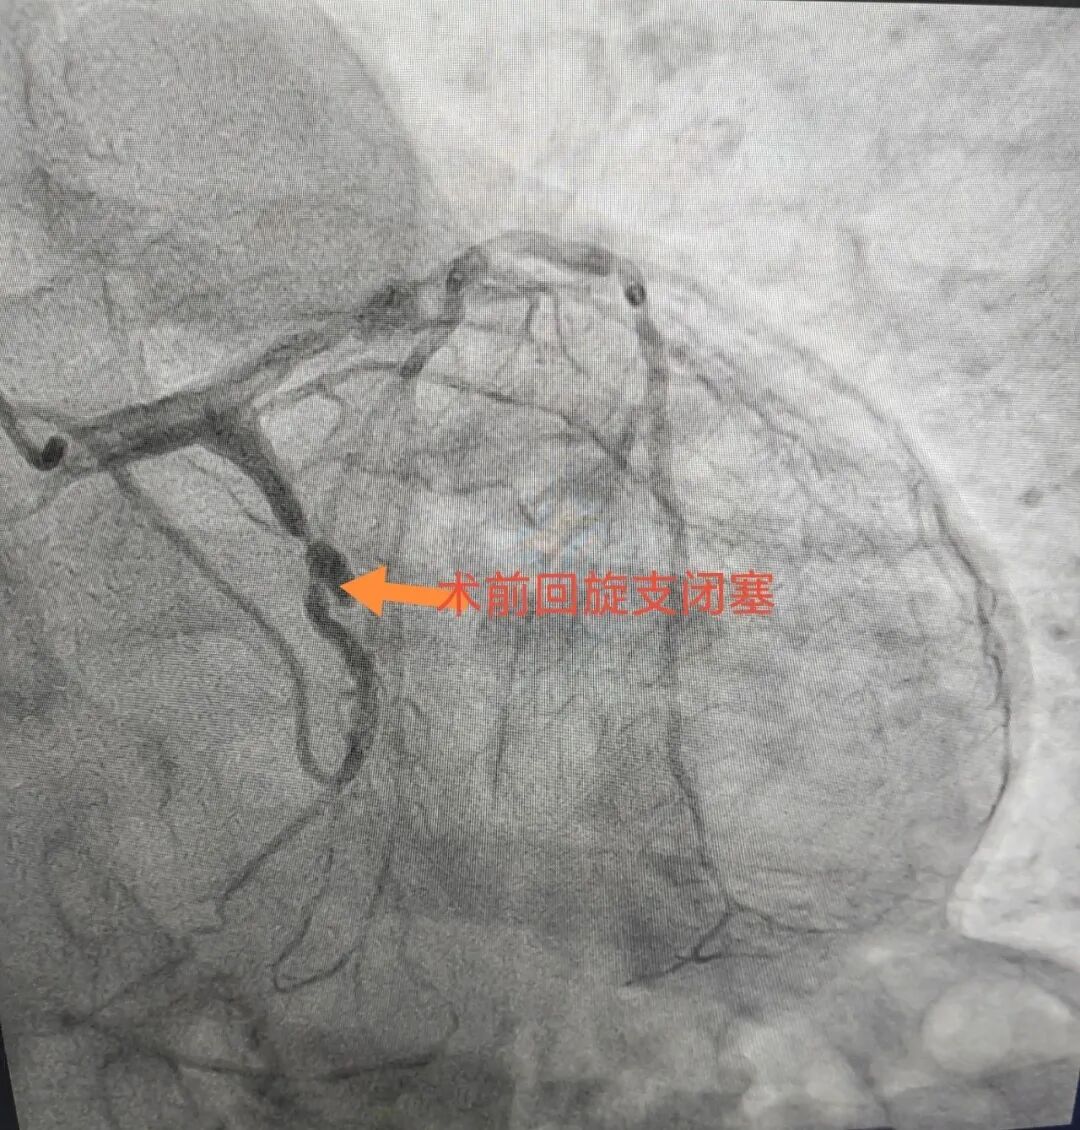

介入导管室的医生们都有一双“穿针引线的巧手”,他们凭借穿刺针、导管、导丝进行微创操作,疏通原本堵塞的血管,点燃患者生命之光。为了手术方便,介入医生们穿的铅衣大多设计成分体式,上半身是铅背心,下半身是铅围裙,而为了保证手臂的灵敏度,胳膊、手、脸、眼睛等部位仍然要裸露在外,并不能完全防止辐射。

北京中医医院内蒙古医院心病科现有北京常驻专家两名,科室为国家中医优势专科,自治区中医临床重点专科,自治区中医特色重点专科,市级中医重点专科,中国急性心肌梗死规范化救治项目内蒙古救治协作分中心,国家心血管病中心高血压专病医联体,国家标准化心脏康复中心建设单位。科室开展急诊冠脉介入,复杂冠脉介入,精准冠脉介入等技术。在冠心病,心功能不全,高血压,心律失常、糖尿病等方面充分发挥中西医结合优势,提高临床疗效,减少患者再住院率,提高患者生活质量,得到广大患者的好评。